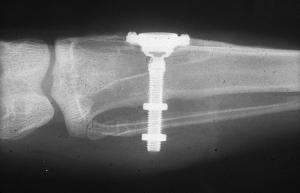

Branemark’s_initial_radiograph